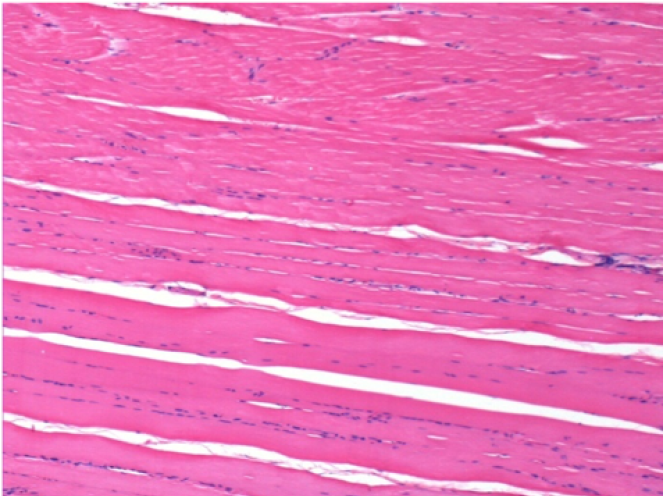

08

3 mesi dopo Iniezione di Endopeel

Scatola Nr 4

3 mesi (Giorno90) dopo iniezione 0.1ml di Endopeel nel muscolo pretibiale destro ( Dx)

Sx : Controllo-100x-Giorno90

Dx:100x-Giorno90